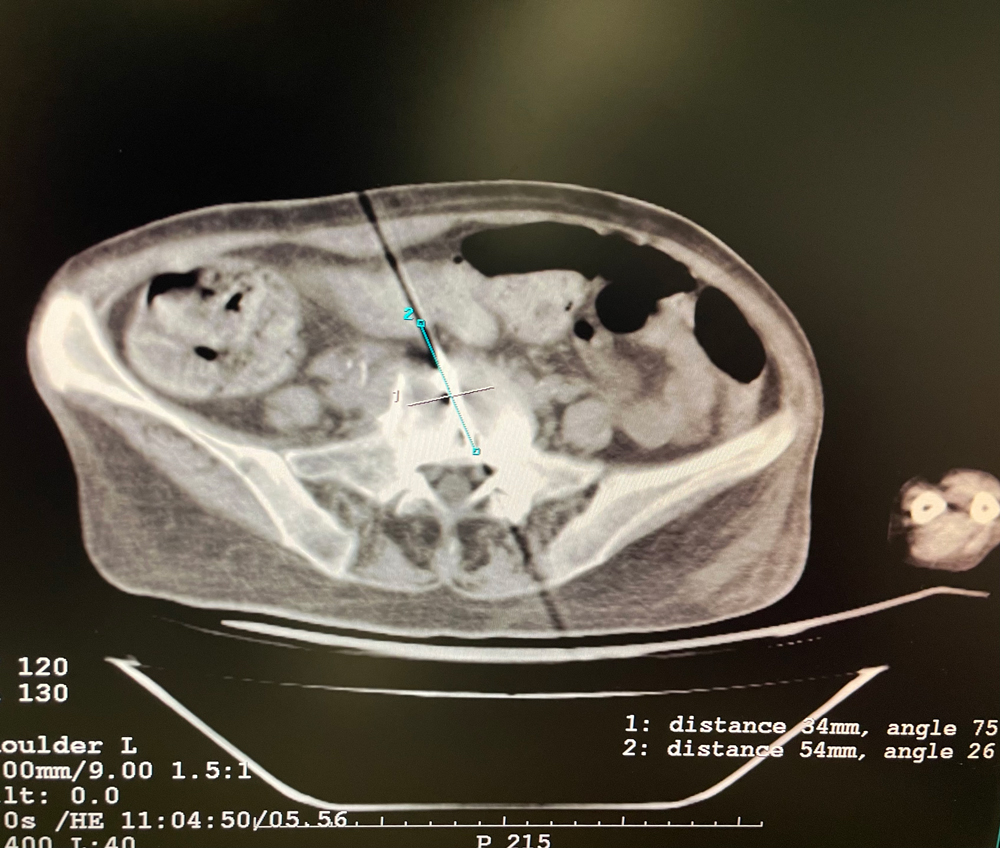

女,42岁,复发性脂肪瘤,病灶位于右侧膝关节,直径大小13cm。采用双针方案,共进行6个冻融循环,最大冰球直径达8.2cm,术中多方位治疗全面覆盖病灶范围。患者术后状况良好。